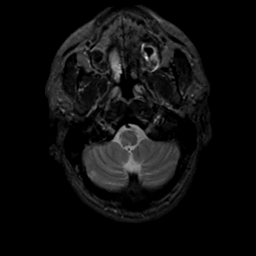

MR Study #3, February 24, 1991 -- Slice #5

[Home][Help][Clinical][Tour 1][Tour 2] Slice 5